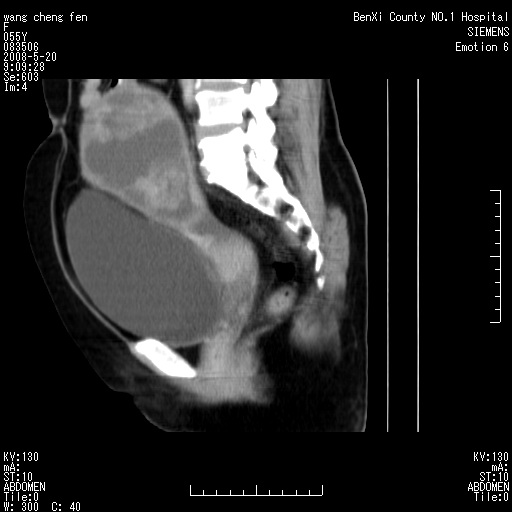

标题: CT3539:盆腔巨大肿瘤增强 [打印本页]

标题: CT3539:盆腔巨大肿瘤增强

女、绝经后阴道流血3个月

宫颈略萎缩、宫颈前唇及阴道前臂可初级结节。

左侧附件区可见一囊性占位,边缘清楚,内可见不规则形软组织影 ce:囊壁及内部可见强化 考虑 卵巢囊腺瘤

左侧附件区巨大囊实性病灶,边缘光整,病灶囊壁较厚,增强示囊壁及实性部分明显强化,强化呈度与宫体实质大致相同,宫腔积液征像,未见盆腔积液等其他异常,考虑左侧卵巢囊腺癌,不除外囊腺瘤及浆膜下肌瘤坏死

左侧附件区巨大囊实性病灶,边缘光整,病灶囊壁较厚,增强示囊壁及实性部分明显强化,强化呈度与宫体实质大致相同,宫腔积液征像,未见盆腔积液等其他异常。绝经后阴道流血3个月,结合病史左侧卵巢囊腺癌首先考虑,宫腔扩大不除外累及。期待结果。